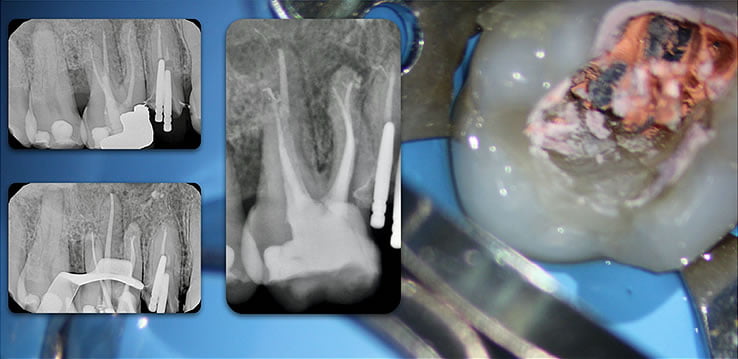

Template for x-rays

Biolight® DRILL-FREE posts are available in bundles of 4, 6, 9 and 12 strands. The post size is selected based on the width of the canal at the coronal area. Depending upon the canal width at the apical stop, a certain number of strands must be pushed to the stop. Both of the measurements are made with the assistance of a radiograph and the template that is included in the TRAINING KIT.